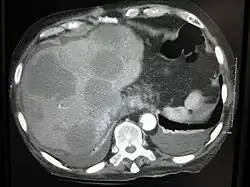

CT image of multiple liver metastases -